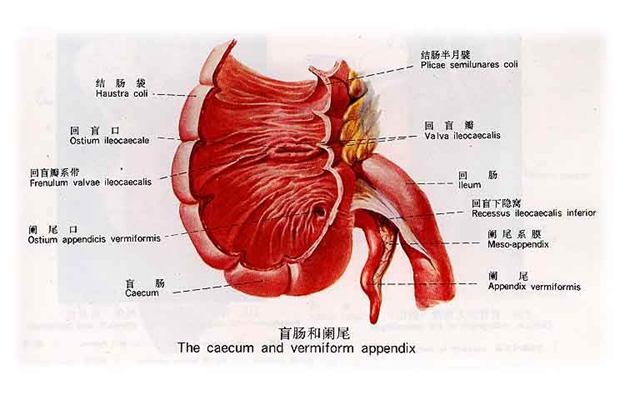

盲腸炎圖片

盲腸的位置 (50)

盲腸的位置 (6)

盲腸的位置 (7)

盲腸的位置 (8)

盲腸的位置 (9)

盲腸的位置 (46)

盲腸的位置 (47)

盲腸的位置 (48)

盲腸的位置 (49)

盲腸的位置 (5)